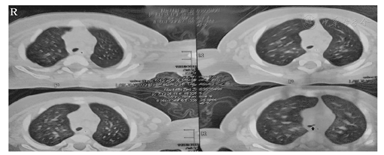

行支气管镜检查示:气管通畅,隆突结构畸形,隆突水平气管分为左右两支,左侧分支开口狭窄为著(图2)。行CT气管-支气管三维重建示:桥支气管(图3)。建议行手术治疗,患儿家属因手术风险等原因不同意,继续内科保守治疗8 d,病情无缓解,无创呼吸机无法脱机,患儿家属放弃治疗,出院第2天夜间患儿死亡。

箭头1所示为起源于气管的右肺上叶和中叶干支气管。箭头2所示为狭窄的桥支气管。箭头3所示为起源于左主支气管的右肺下叶支气管。